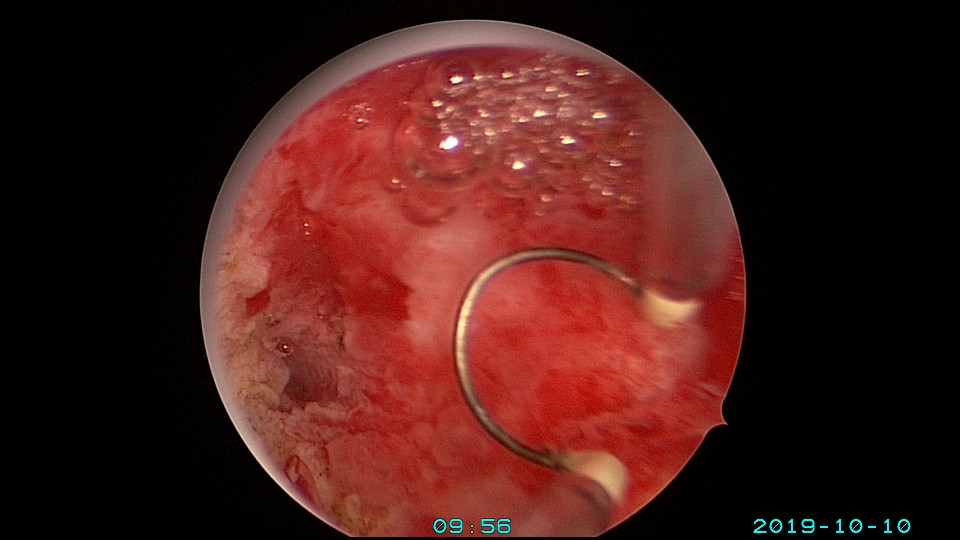

患者26岁,G1P0 ,2019年9月门诊宫腔镜检查发现宫腔重度粘连,2019年10月住院宫腔镜分粘,恢复宫腔形态,显露双侧输卵管开口。2019年11月宫腔镜二探取球囊,宫腔形态正常,双侧输卵管开口可见。2021年3月发现自然妊娠,后因先兆流产、胎心弱在当地医院险些清宫终止妊娠,病人电话咨询我,嘱病人千万不要急着清宫,立即到我院复查,心管搏动良好,住院保胎成功,2021年11月,39周孕剖宫产分娩。2023年7月,再次自然妊娠,39+3周孕剖宫产分娩。现31岁,G3P2。